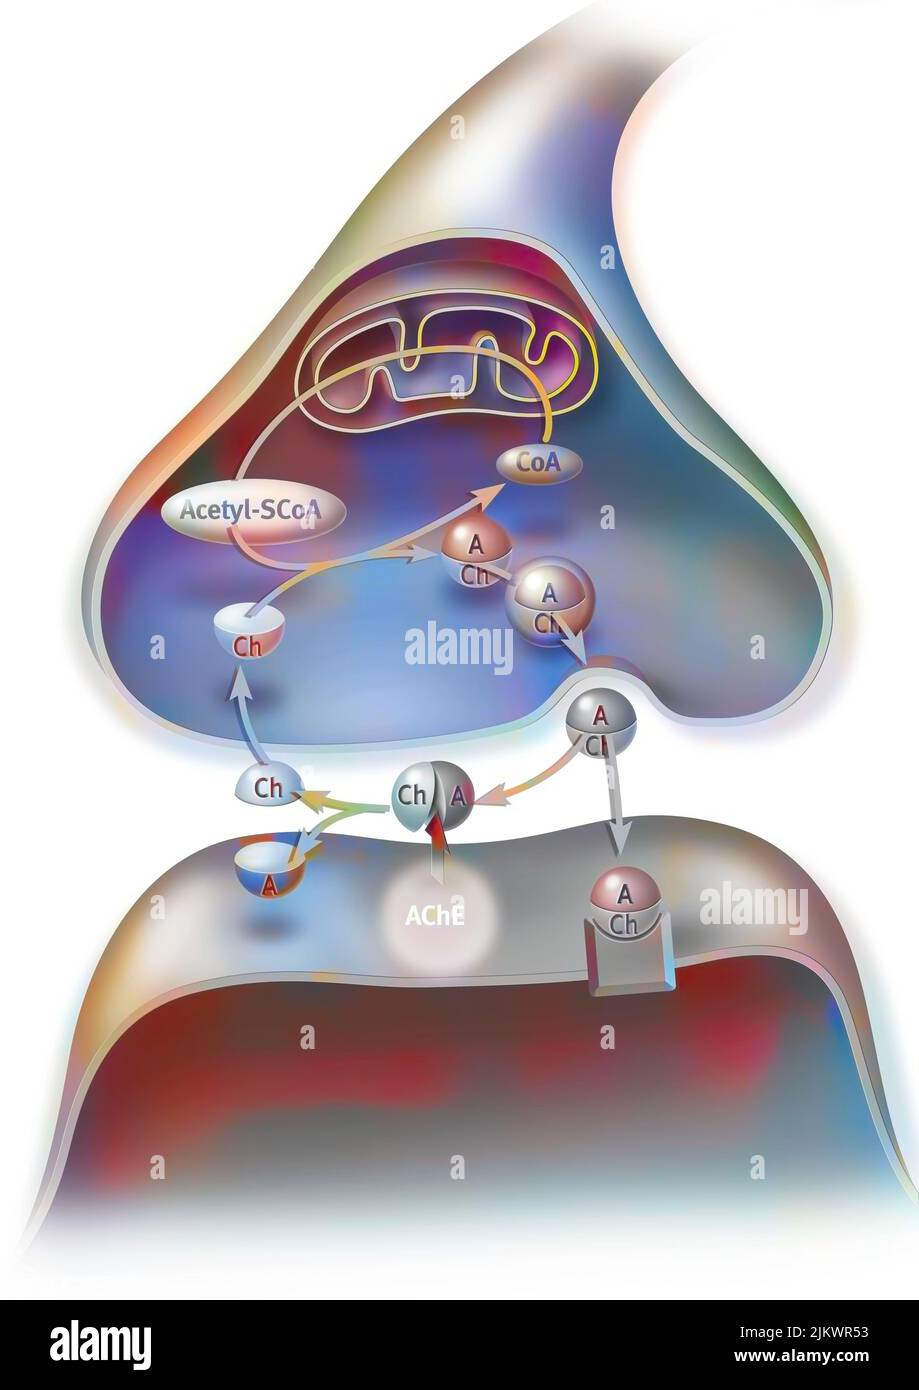

RF2JKWR03–Action des sels minéraux et des vitamines sur la transmission des impulsions nerveuses aux synapses.